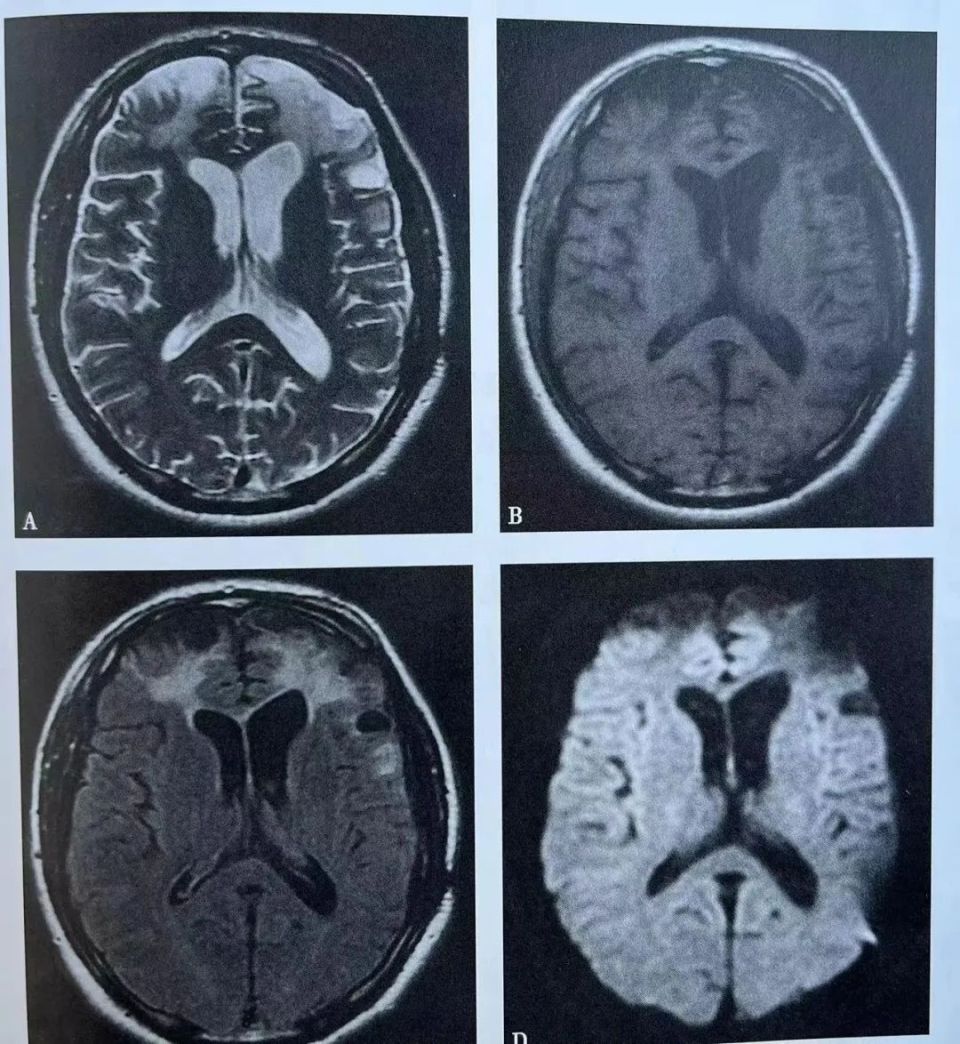

小心误诊这可不是单纯的脑萎缩

局限性脑萎缩的分类及影像学表现